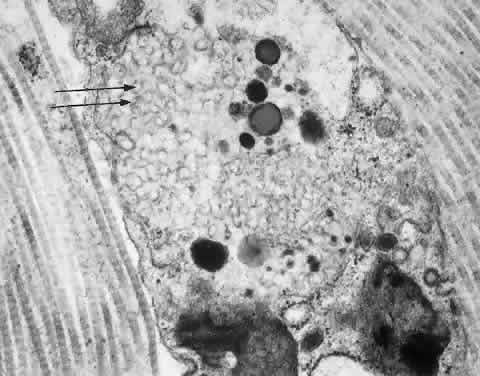

Spranger and Wiedemann coined the term mucolipidoses for this group of disorders.58 The mucolipidoses have phenotypic and biochemical features of both the mucopolysaccharidoses and the sphingolipidoses without excessive urinary excretion of mucopolysaccharides. Ultrastructurally, the affected cells resemble those of the MPSs, with cytoplasmic vacuoles filled with fine fibrillogranular-material. The vacuoles also contain membranous lamellar inclusions similar to those present in the lipidoses.15

Early in the course of the disease, the corneas are clear. Late corneal clouding is common; it correlates positively with survival and occurs in 40% of cases.67 Corneal opacities are evident on slit-lamp examination as diffuse stromal granules. Glaucoma occurs in 6% of patients.68 No cherry-red macula is present. Conjunctival biopsy is diagnostic.68